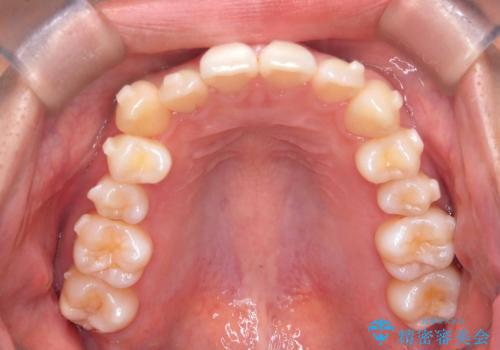

非抜歯矯正で八重歯を改善|短期間8か月で美しい歯並びに|インビザラインライト上顎のみで矯正

- 「八重歯を治したい」との主訴でご来院された患者様です。。

非抜歯で上顎のみインビザラインライトを使用して矯正を行いました。

短期間(約8か月)の治療で歯並びが整い、患者様も大変喜ばれました。